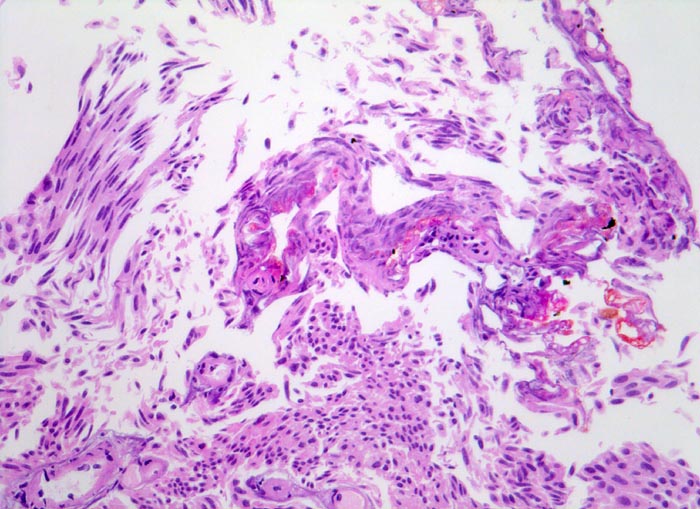

Morphologische Merkmale:

• Transurethrale Resektate von Harnblasenschleimhaut mit papillärem Tumor.

• Entnahmebedingte Kauterartefakte (dünn ausgezogene Zellen und Chromatinschlieren, ausgefranste Abtragungsränder).

• Das neoplastische Urothel bildet fingerförmige, teils miteinander verschmelzende Papillen mit schmalen fibrovaskulären Stromastielen.

• Das neoplastische Urothel ist verbreitert (meist mehr als 7 Zellagen).

• Scharfe Grenze zwischen Epithel und subepithelialem Stroma (keine Invasion).

• Mässiggradige Dysplasie des neoplastischen Urothels (G2, low grade): Tumorzellen mit vergrösserten, leicht pleomorphen Zellkernen. Zahlreiche Apoptosen. Herdförmiger Polaritätsverlust (fehlende Ausrichtung der Zellen in der Längsachse).

• Auf diesem Schnittpräparat sind kein tumorfernes Urothel und keine Anteile der Harnblasenwandmuskulatur enthalten.